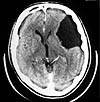

КТ в неврологии. Группа современных диагностических процедур с использованием рентгеновских лучей, которые позволяют получать послойные изображения «срезов» черепа, позвоночника, головного и спинного мозга, которые хорошо отражают особенности реальной структуры перечисленных анатомических структур. Это открывает возможности для диагностики врожденных патологий, травматических повреждений, воспалительных и сосудистых заболеваний, первичных опухолей и метастазов. Для повышения точности изображения при проведении КТ в неврологии дополнительно используются специальные контрастные вещества.

Компьютерная томография в неврологии широко используется для выявления аномалий развития и инфекционных поражений центральной нервной системы, последствий черепно-мозговых травм и повреждений позвоночника, объемных поражений (опухоли, кисты, внутримозговая гематома) и нарушений кровообращения головного мозга. и спинной мозг. С помощью оцифровки они планируют тактику следующего нейрохирургического вмешательства и оценивают его эффективность. При КТ в неврологии используется МРТ, но для сравнения компьютерная томография является более доступным и менее трудоемким методом исследования. На компьютерной томографии более четко отображаются твердые структуры - кости черепа, позвоночник и кальцификации, тогда как МРТ лучше подходит для исследования мягких тканей - веществ в головном и спинном мозге, хрящевые и нервные волокна. Следовательно, КТ часто назначают в процессе диагностики ран и аномалий костей, а также при наличии противопоказаний к МРТ из-за наличия в организме искусственных имплантатов (кардиостимулятор, металл ).